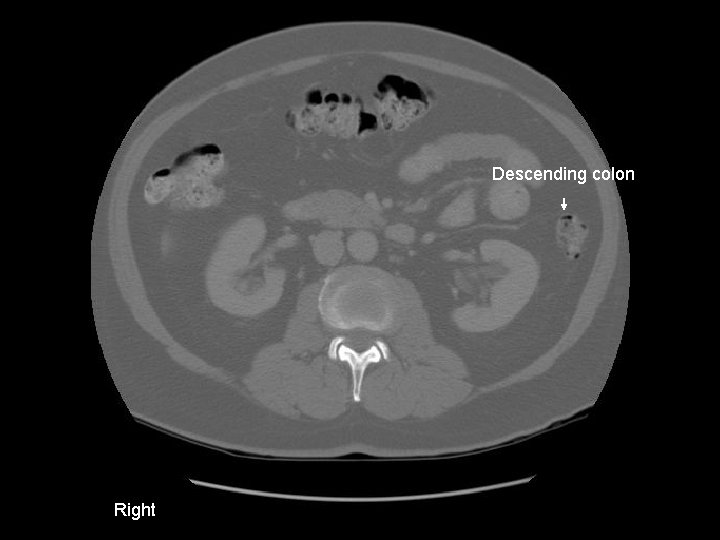

Descending colon Right